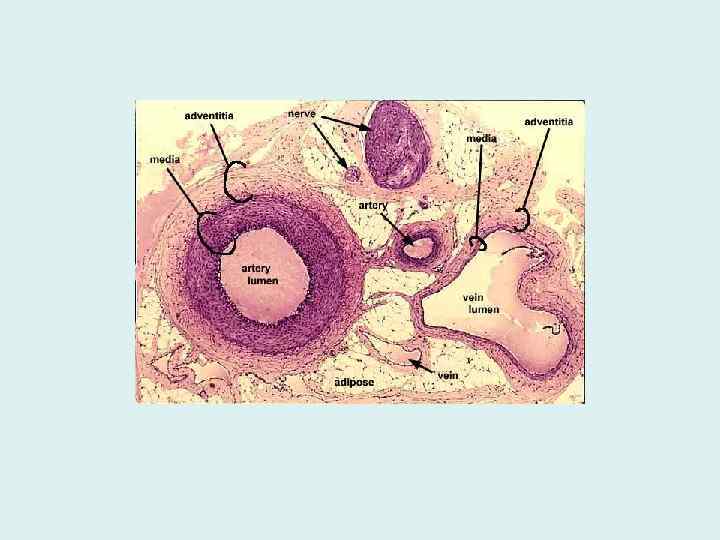

Особенности строения вен • 1. Эластические элементы: подэндотелиальный слой в их t. intima выражен относительно слабо, содержание эластических элементов — гораздо меньше, чем в артериях, в венах (кроме нижней полой вены и вен сердца) обычно нет внутренней эластической мембраны.

4. Соотношение оболочек • у вен обычно (хотя не всегда) более всего выражена t. externa. В артериях самой толстой оболочкой всегда является t. media.

• 5. Vasa vasorum: кровь в венах обеднена кислородом и питательными веществами, она не может снабжать ими внутреннюю и среднюю оболочки сосуда (как у артерий). Поэтому в венах питающие артериальные веточки (vasa vasorum) содержатся во всех оболочках стенки сосуда (а не только в t. externa, как у артерий); капилляры же открываются непосредственно в просвет вен.